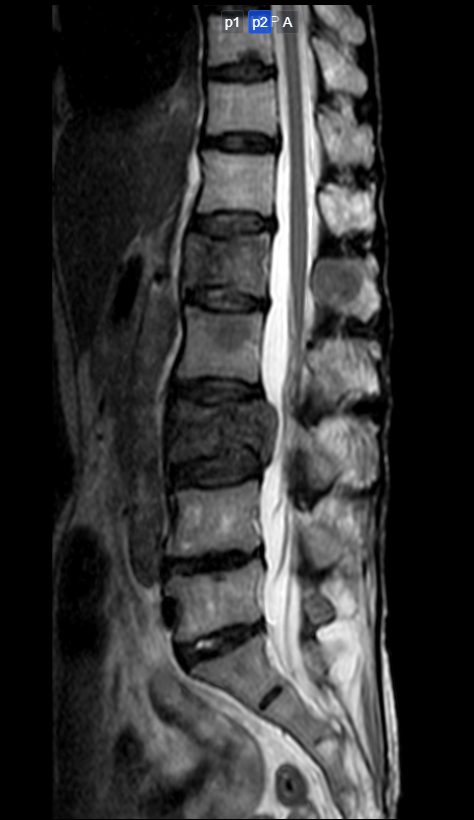

圖片7.png

磁共振提示:多發(fā)椎體及附件轉(zhuǎn)移瘤,其中腰1、3椎體骨質(zhì)破壞較明顯伴腰3椎管占位神經(jīng)受壓。

基于目前最新NOMS決策框架,需要根據(jù)每一位脊柱轉(zhuǎn)移瘤患者的全身情況選擇個(gè)性化的治療方式。由于患者Tomita評(píng)分8分(Tomita評(píng)分最高10分,評(píng)分越高,預(yù)后越差)、Tokuhashi評(píng)分2分(患者Tokuhashi總分0-8分地預(yù)期生存期不足6個(gè)月),經(jīng)住院檢查發(fā)現(xiàn)有低蛋白血癥及貧血,綜合評(píng)估其身體條件并不適合較大創(chuàng)傷手術(shù)。歐清彬副主任醫(yī)師團(tuán)隊(duì)與患者和家屬充分溝通后,決定為患者實(shí)施姑息性固定減壓手術(shù),即采用微創(chuàng)釘棒系統(tǒng)固定+部分椎板切除減壓以獲得即刻穩(wěn)定及解除神經(jīng)壓迫保護(hù)神經(jīng)功能。